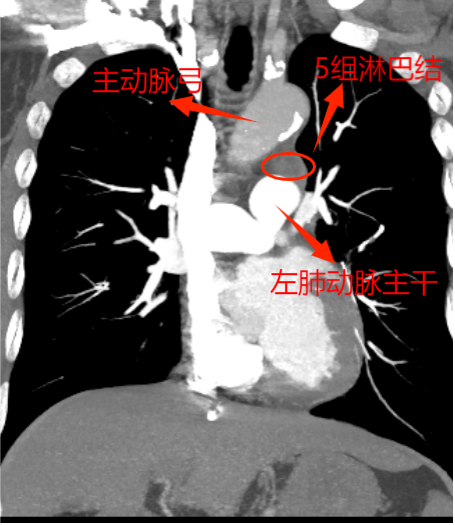

這下讓外科手術(shù)團隊為難了,因為兩組淋巴結(jié)臨近主動脈及左肺動脈2處大血管,位置深,即使CT引導下穿刺活檢,僅毫厘之差,仍大概率會出現(xiàn)大出血、氣胸,甚至危及生命,需緊急開胸,不活檢。由于轉(zhuǎn)移瘤性質(zhì)難定,影響后續(xù)方案的制定,家屬也很焦慮。

為實現(xiàn)更微創(chuàng),手術(shù)采取了單孔胸腔鏡技術(shù)。此次手術(shù),慶幸的是左肺與胸腔粘連不嚴重,但5、6組轉(zhuǎn)移淋巴結(jié)又硬又緊,與周圍組織界限欠清,尤其是5組淋巴結(jié),深埋進主動脈弓與左肺動脈根部,左主支氣管間,旁邊還有重要的迷走神經(jīng)及喉返神經(jīng)。血管損傷可能導致大量出血,神經(jīng)損傷可能造成聲音嘶啞、飲水嗆咳等并發(fā)癥。